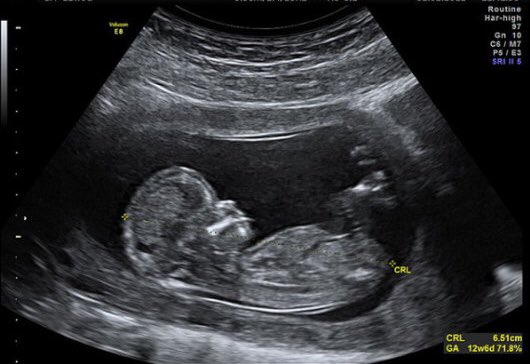

Узи 12 13

Узи 12 13 112 фото